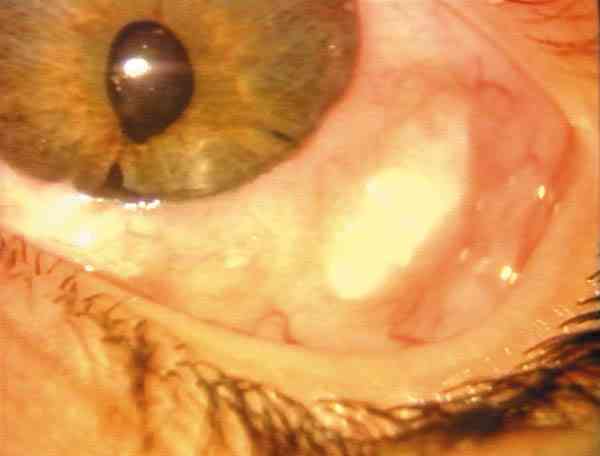

B. Desprendimientos coroideos y retinianos exudativos: Se une al apartado anterior como queda referido, y es típica del síndrome de Sturge-Weber (figura 7) y también de ojos buftálmicos afáquicos, generalmente poliintervenidos. Suelen resolverse sin dar lugar a otras complicaciones.

08-07.jpg (30095 bytes)

Figura 7. Trabeculectomía en el Síndrome de Sturge-Weber: a) Síndrome de Sturge-Weber; b) Angioma epiescleral; c) Desprendimiento retiniano exudativo; d) Ecografía de un desprendimiento coroideo.